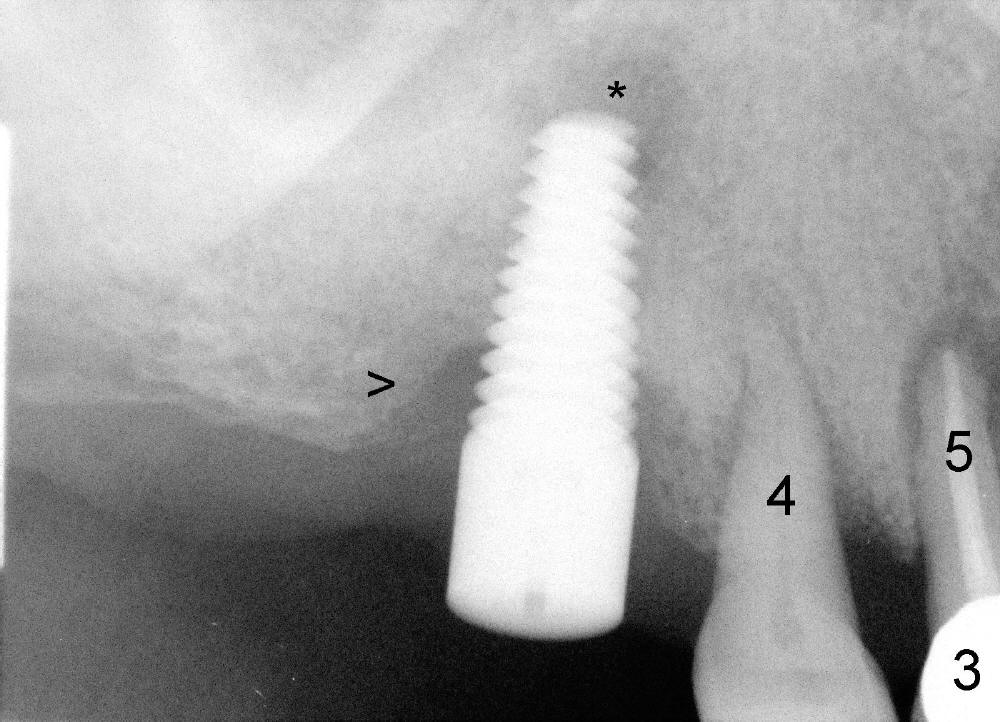

A 42-year-old man has poor dentition with missing multiple teeth. He was a smoker. After smoke cessation, two implants are placed at the sites of #3 (6x17mm) and 19 (5x14mm) (Fig.1,2). It does not sound great to place #3 implant close to a potential infection site (#5, Fig.1). But the latter is asymptomatic. Four months post #3 implantation, he returns with pain in the upper right sextant (Fig.3). The tooth #18 appears to shift mesially (Fig.4). To place a crown over #19 implant, the mesial surface of the crown of #18 has to be trimmed. What cannot be done associated with #18 shifting is food impaction between #17 and 18 (Fig.8). Clinical exam reveals crack of the tooth #4. Immediate implant is planned. Is it too close to the infection site?